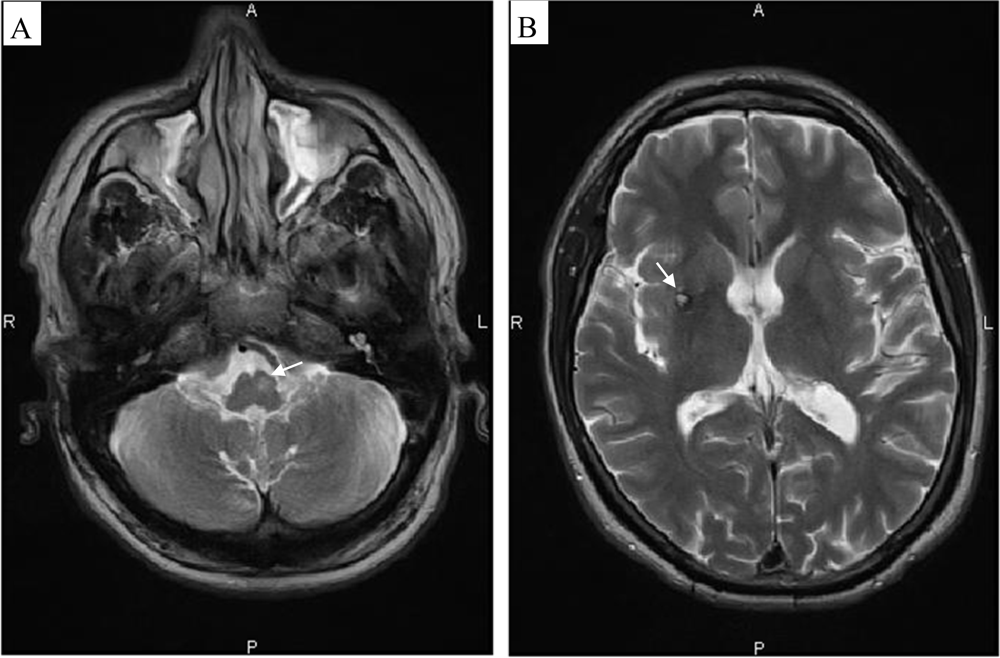

- Döhlinger, S.; Hauser, T.K.; Borkert, J.; Luft, A.R.; Schulz, J.B. Magnetic resonance imaging in spinocerebellar ataxias. Cerebellum 2008, 7, 204–214. [Google Scholar]

| Brain imaging (CT-scan - MRI - SPECT- PET) |